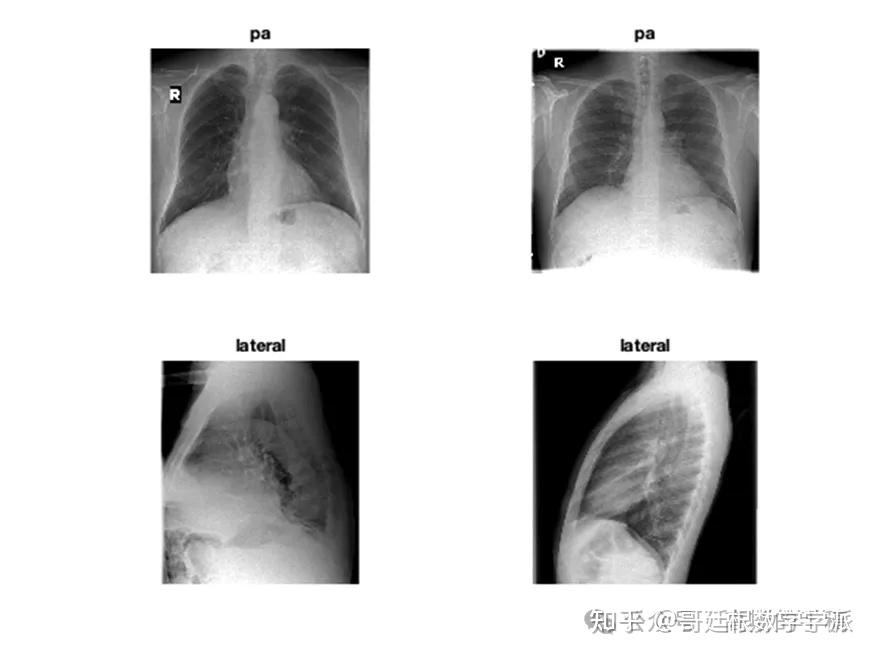

医学图像的深度学习可解释性(MATLAB R2021B)